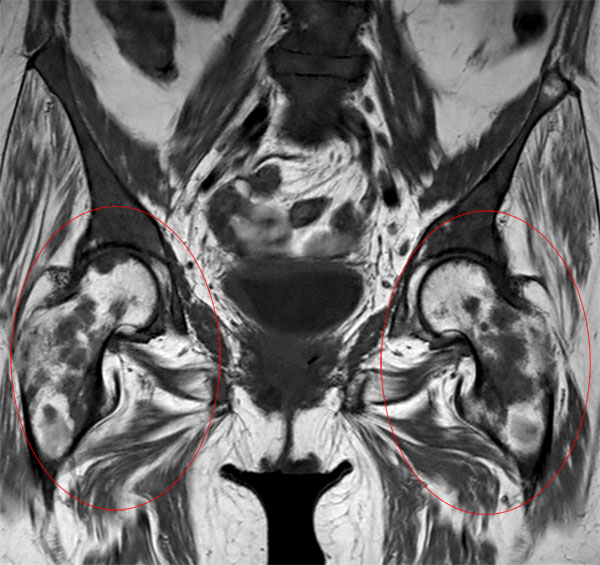

Patient with bone lesions.